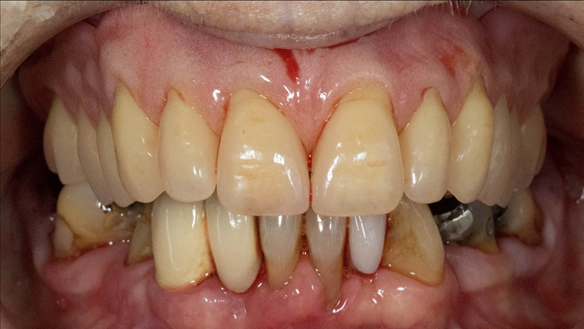

- The remaining natural upper natural teeth and lower back molars were heavily restored having generalised periodontitis stage 4 Grade C. Some of the teeth exhibited caries. The prognosis for these teeth ranged from dubious to hopeless.

- The upper and lower acrylic based partial dentures exhibited suboptimal extension of the flanges and saddles. They had poor retention, support, stability and tissue fit.

- The patient had a high smile line showing 5mm or more alveolar soft tissue above the upper front teeth during social interaction.

The clinical situation and treatment process is shown in detail below with photographs. In addition, threre is a link to the a 45 minute webinar I gave explaing this case. I provided the clinical work and Rowan Garstang provided the technical work.